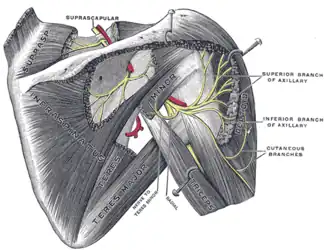

Suprascapular and axillary nerves of right side, seen from behind.

Suprascapular and axillary nerves of right side, seen from behind.